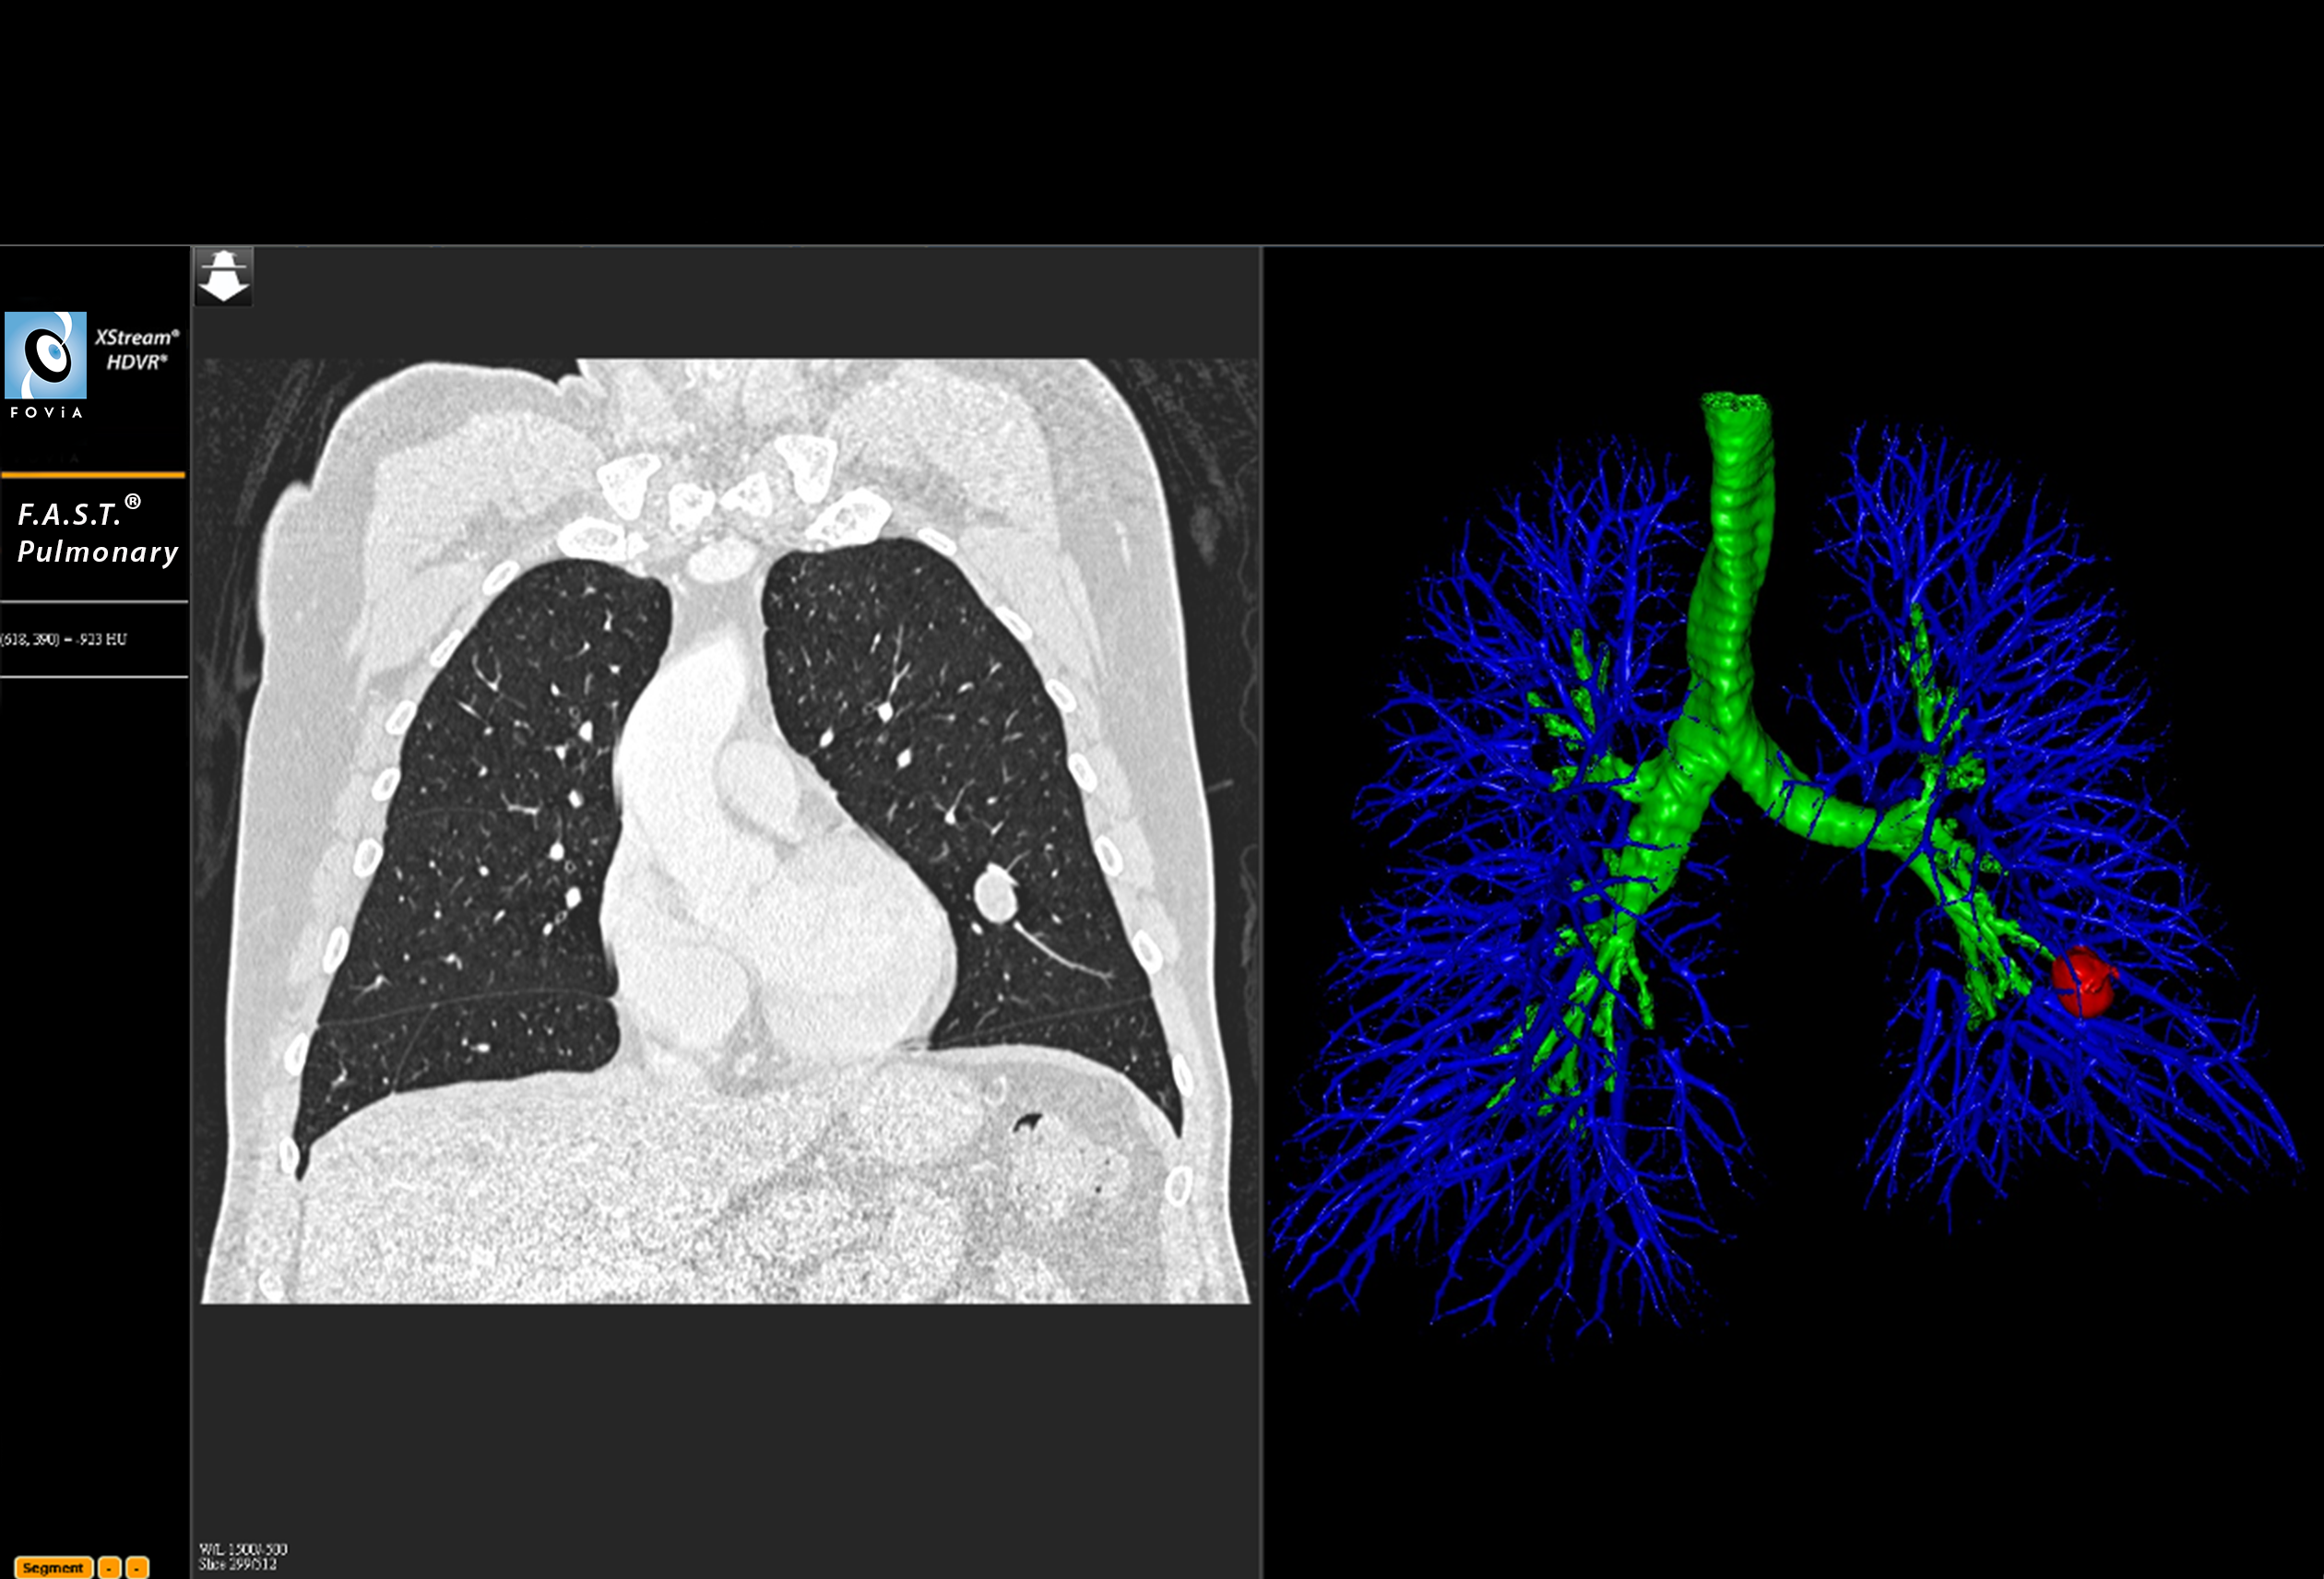

F.A.S.T. Pulmonary Workflow

F.A.S.T. Pulmonary Workflow